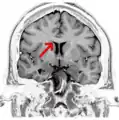

Sagittal section of brain, front part to the left. The corpus callosum can be seen in the center, in light gray

The corpus callosum forms the floor of the longitudinal fissure that separates the two cerebral hemispheres. Part of the corpus callosum forms the roof of the lateral ventricles.[5]

The corpus callosum has four main parts – individual nerve tracts that connect different parts of the hemispheres. These are the rostrum, the genu, the trunk or body, and the splenium.[4] A narrowed part between the trunk and the splenium is known as the isthmus. Fibres from the trunk and the splenium known together as the tapetum form the roof of each lateral ventricle.[6]